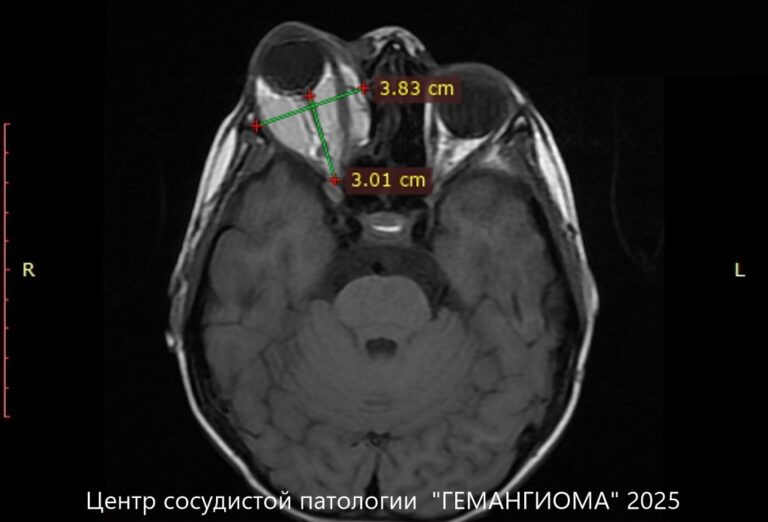

Мама мальчика тут же с нами связалась, но возможности оперативно приехать на очный прием не было, поскольку проживали они в другой стране. Поэтому мы назначили им проведение МРТ (это ключевое исследование при данной патологии).

Полость мальформации, которая находилась за глазным яблоком, наполнялась кровью и выталкивала глаз вперед. Через некоторое время глаз ребенка перестал закрываться, на ночь приходилось заклеивать его специальными окклюдерами, а в течение дня постоянно использовать офтальмологические капли и гели, чтобы глаз не пересыхал. В данной ситуации было необходимо хирургическое вмешательство, поскольку из-за наличия мальформации самостоятельно патологические полости опорожниться не могли.

Получив данные обследования, у нас была точная картина того, что происходит в области орбиты и мы могли составить план лечения. Было решено проводить очередной этап склерозирования, несмотря на сложный доступ к полости мальформации, которая находилась глубоко в орбите.

Через месяц на контрольном МРТ обследовании было отмечено, что полости мальформации значительно уменьшились.